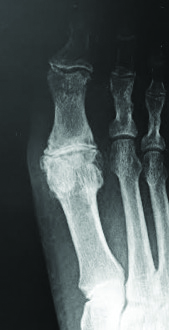

Stage 1. In stage 1 of the classification system, only 30 to 40 degrees of dorsiflexion is available for the hallux to dorsiflex passively.11 Furthermore, we begin to see dorsal spurring radiographically with minimal narrowing of the joint space. The patient consequently begins to experience slight pain but usually only at the end range of motion and not consistently. These clinical and radiographic findings correspond to early structural hallux limitus.

Stage 2. In stage 2, there is a more dramatic loss in dorsiflexion at the first MPJ (10 to 30 degrees of dorsiflexion remaining), which can make ambulation both difficult and painful.11 On radiographs, we again see dorsal osteophytes but they will be more extensive than in stage 1, and there will be a further decrease in joint space. While this stage still represents a structural hallux limitus, the severity of joint destruction at this point in the progression of the disorder necessitates a different approach to treatment than the previous stages. Instead of attempting to increase motion, which would continue to cause the patient pain, we would like to limit the remaining motion available at the joint.

Stage 3. In stage 3, the patient has lost nearly all motion in the first MPJ (less than 10 degrees of dorsiflexion remaining) and movement of the joint to end range causes the patient significant pain.11 Joint space narrowing is substantial and the sesamoids may be affected. This stage would correspond to a hallux rigidus by definition.